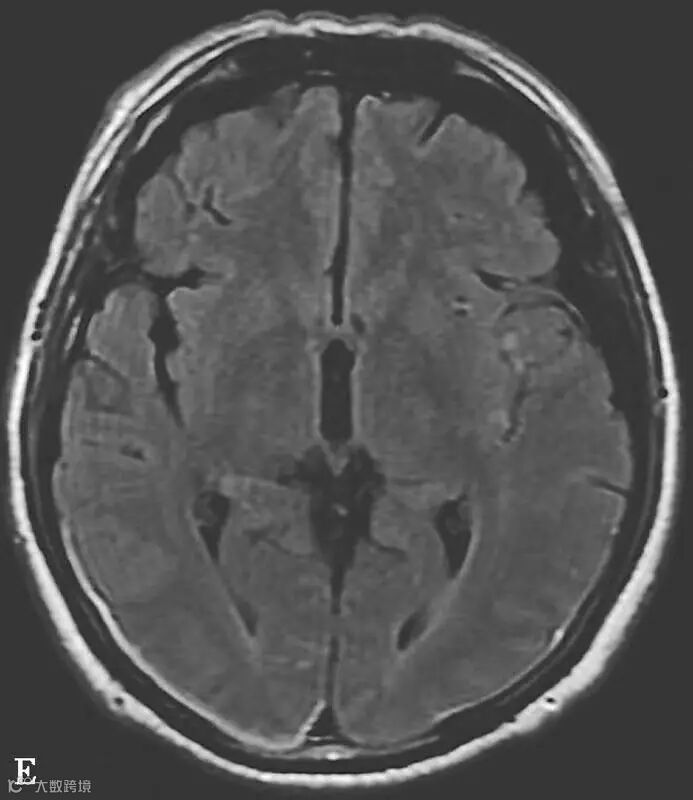

图6-11-1 弥漫性轴索损伤并双侧额部硬膜下积液、双侧顶枕部硬膜下血肿

男,34岁,外伤后7天。A~H(A、B.T2WI,C、D.T1WI,E、F.T2WI-FLAIR,G、H.DWI):左侧岛叶及右侧顶叶白质可见斑片状稍长T1稍长T2信号,边缘不清,FLAIR及DWI呈高信号。双侧额部内板下可见新月形长T1长T2信号,FLAIR及DWI呈低信号。双侧顶枕部内板下可见弧形短T1长T2信号,FLAIR及DWI呈高信号